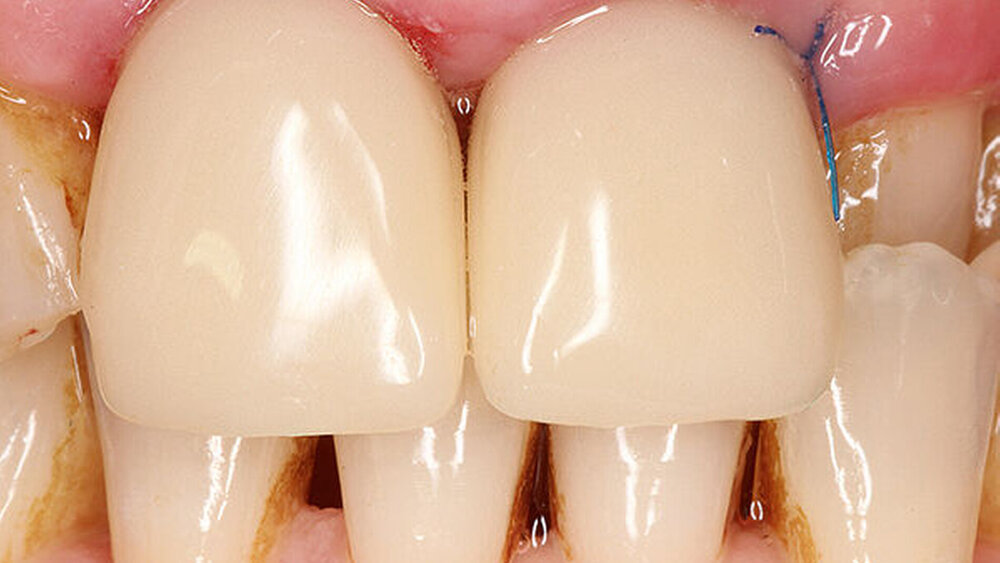

Zusätzlich kann das Emergenzprofil bereits intraoperativ in der Implantationssitzung gesteuert werden. Der Scan der ausgeheilten Situation vor der prothetischen Versorgung eröffnet die Möglichkeit, durch Einmatchen des Implantats in den Datensatz die subgingivale Situation zu simulieren ohne die Darstellung einer „Präparationsgrenze“ durch das Einlegen von Fäden. Diese Manipulationen sind traumatisch und zerstören die sensible hemidesmosomale Anhaftung der Gingiva- und Bindegewebsfasern an der Implantatoberfläche. Der digitale Abdruck wird die konventionelle Abformung in der modernen Zahnarztpraxis aufgrund seiner überlegenen Performance ersetzen. Den parodontologischen und minimalinvasiven Prinzipien folgend, ist die digitale Abformung von Zähnen auch in der ästhetisch sensiblen Zone angesichts der geringeren Traumatisierung der parodontalen Gewebe, der überragenden Präzision und der daraus folgenden Randpassung der Versorgung ein logischer und richtiger Weg in die Zukunft der zahnärztlichen Praxis (Abb. 10 – 14).